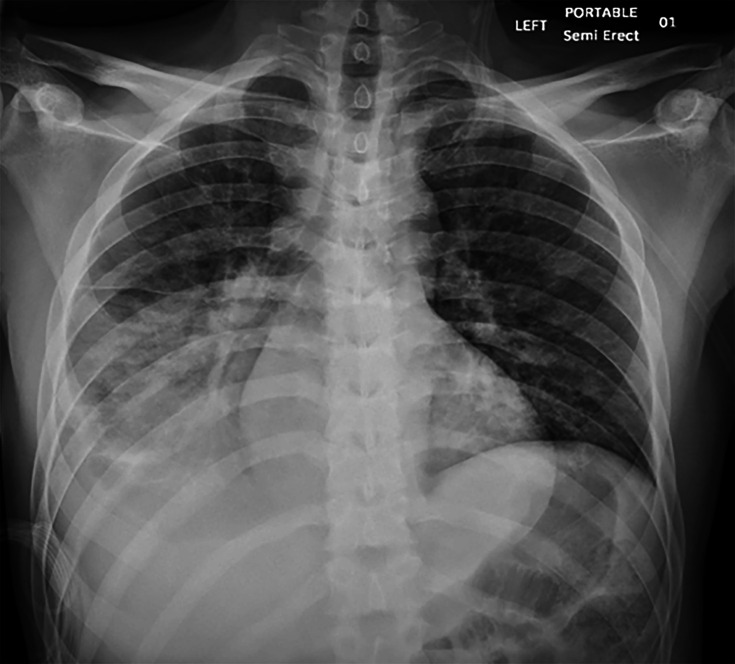

Introduction. Coccidioidomycosis, or Valley fever, is a fungal disease caused by Coccidioides species, prevalent in parts of the southwestern United States. It usually results from inhaling spores from soil and is a common cause of pneumonia in these regions. Case Presentation. We present a unique case of coccidioidomycosis in an immunodeficient male patient secondary to human immunodeficiency virus infection with poor adherence to anti-retroviral treatment. After presenting with non-specific symptoms and pre-syncope, he was initially diagnosed with pneumonia based on chest X-ray findings, but his symptoms failed to improve with antibiotics. He was treated for presumed pulmonary histoplasmosis following a positive histoplasma urine antigen test. However, the patient worsened clinically. Following a computed tomography scan demonstrating a large necrotic lung consolidation, fungal stain and culture of tissue biopsied through endobronchial ultrasound confirmed coccidioidomycosis. The patient received 2 weeks of liposomal amphotericin with clinical improvement before discharge with itraconazole. Conclusion. The histoplasma antigen test can be falsely positive due to cross-reaction with other fungal infections like blastomycosis, paracoccidioidomycosis or talaromycosis, and less frequently, coccidioidomycosis or aspergillosis. Diagnosis of coccidioidomycosis requires a high index of suspicion outside the expected geographic distribution in the appropriate clinical setting. Our case highlights the risk of false-positive antigen test results and the importance of invasive diagnostics, including bronchoscopy to obtain fungal cultures, if the diagnosis remains uncertain.